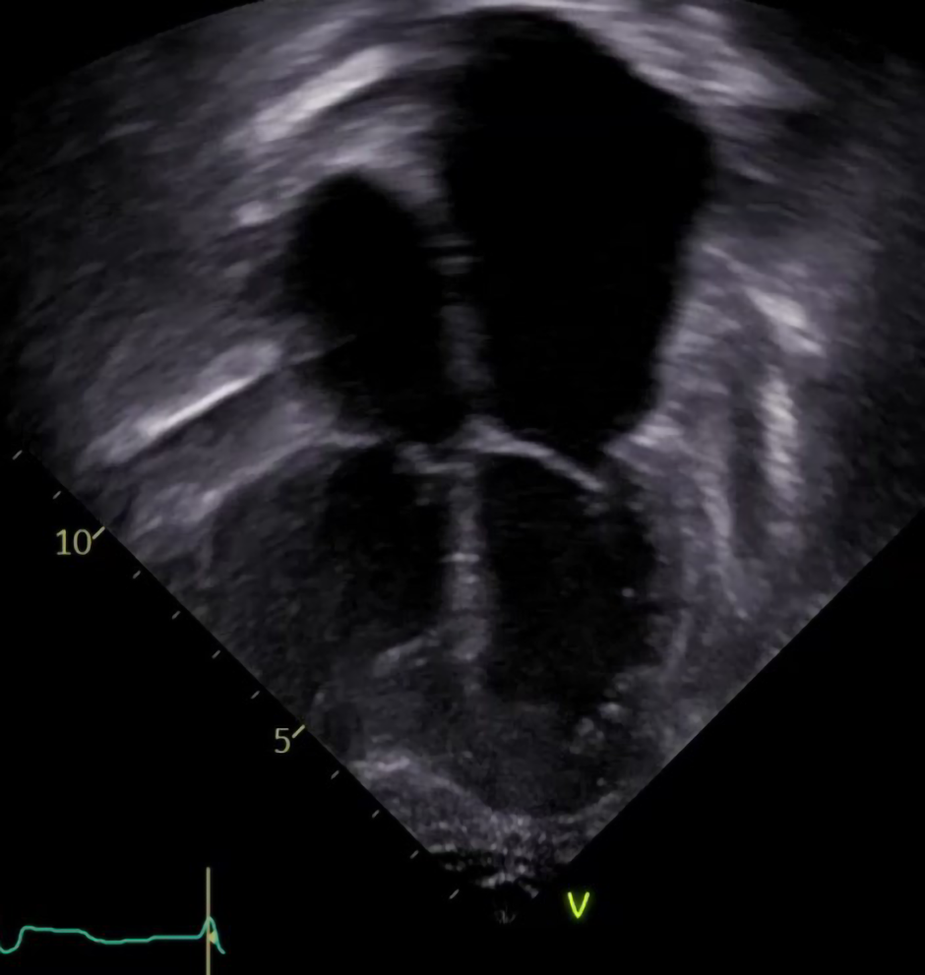

Figure 2

The echocardiographic image illustrates the typical features of chronic graft dysfunction in a child 16 years post heart transplant with CAV and diastolic heart failure. There is marked dilation of the atria, dilation of the pulmonary veins, and normal left ventricular size and function. This patient is 7 years after severe CAV requiring stenting of a focal narrowing of the left anterior descending artery. He remains alive with oral anti-congestive therapies to treat symptoms of his chronic graft dysfunction.